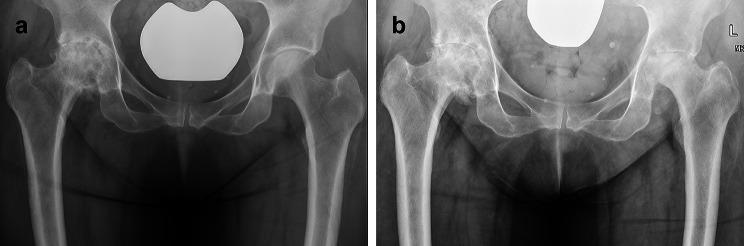

This is a retrospective evaluation of 682 hips that underwent ICSI with 40 mg of Triamcinolone for primary osteoarthritis of the hip. All ICSI were performed using sterile techniques, the number of ICSI in each hip and the cumulative corticosteroid dosage were assessed. Pre- and post-injection radiographs were compared to identify cases with RPIO. Native joint septic arthritis, surgical site infections and PJI were identified by chart review.

4 hips (0.6%) developed RPIO 2-4 months following ICSI. The cumulative Triamcinolone dose was not associated with the development of RPIO (p = 0.281). 1 case was diagnosed with septic arthritis and treated with staged THA, there were no signs of infection at a 5 years follow-up. 483 hips (75.7%) underwent THA, including 199 hips with THA less than 3 months following ICSI and 181 hips with > 1 ICSI prior to THA. There were 3 superficial surgical site infections/wound dehiscence and no PJI.

这是对 682 髋因原发性髋关节骨关节炎接受 40mg 曲安奈德 ICSI 的回顾性评估。所有 ICSI 均采用无菌技术进行,评估每髋 ICSI 的次数和累积皮质类固醇剂量。比较注射前后的 X 线片,以确定 RPIO 病例。通过病历回顾确定原发性关节化脓性关节炎、手术部位感染和 PJI。

4 髋(0.6%)在 ICSI 后 2-4 个月发生 RPIO。累积曲安奈德剂量与 RPIO 的发生无关(p=0.281)。1 例诊断为化脓性关节炎,行分期 THA 治疗,5 年随访时无感染迹象。483 髋(75.7%)接受了 THA,其中 199 髋在 ICSI 后 3 个月内行 THA,181 髋在 THA 前有 >1 次 ICSI。有 3 例浅表手术部位感染/伤口裂开,无 PJI。